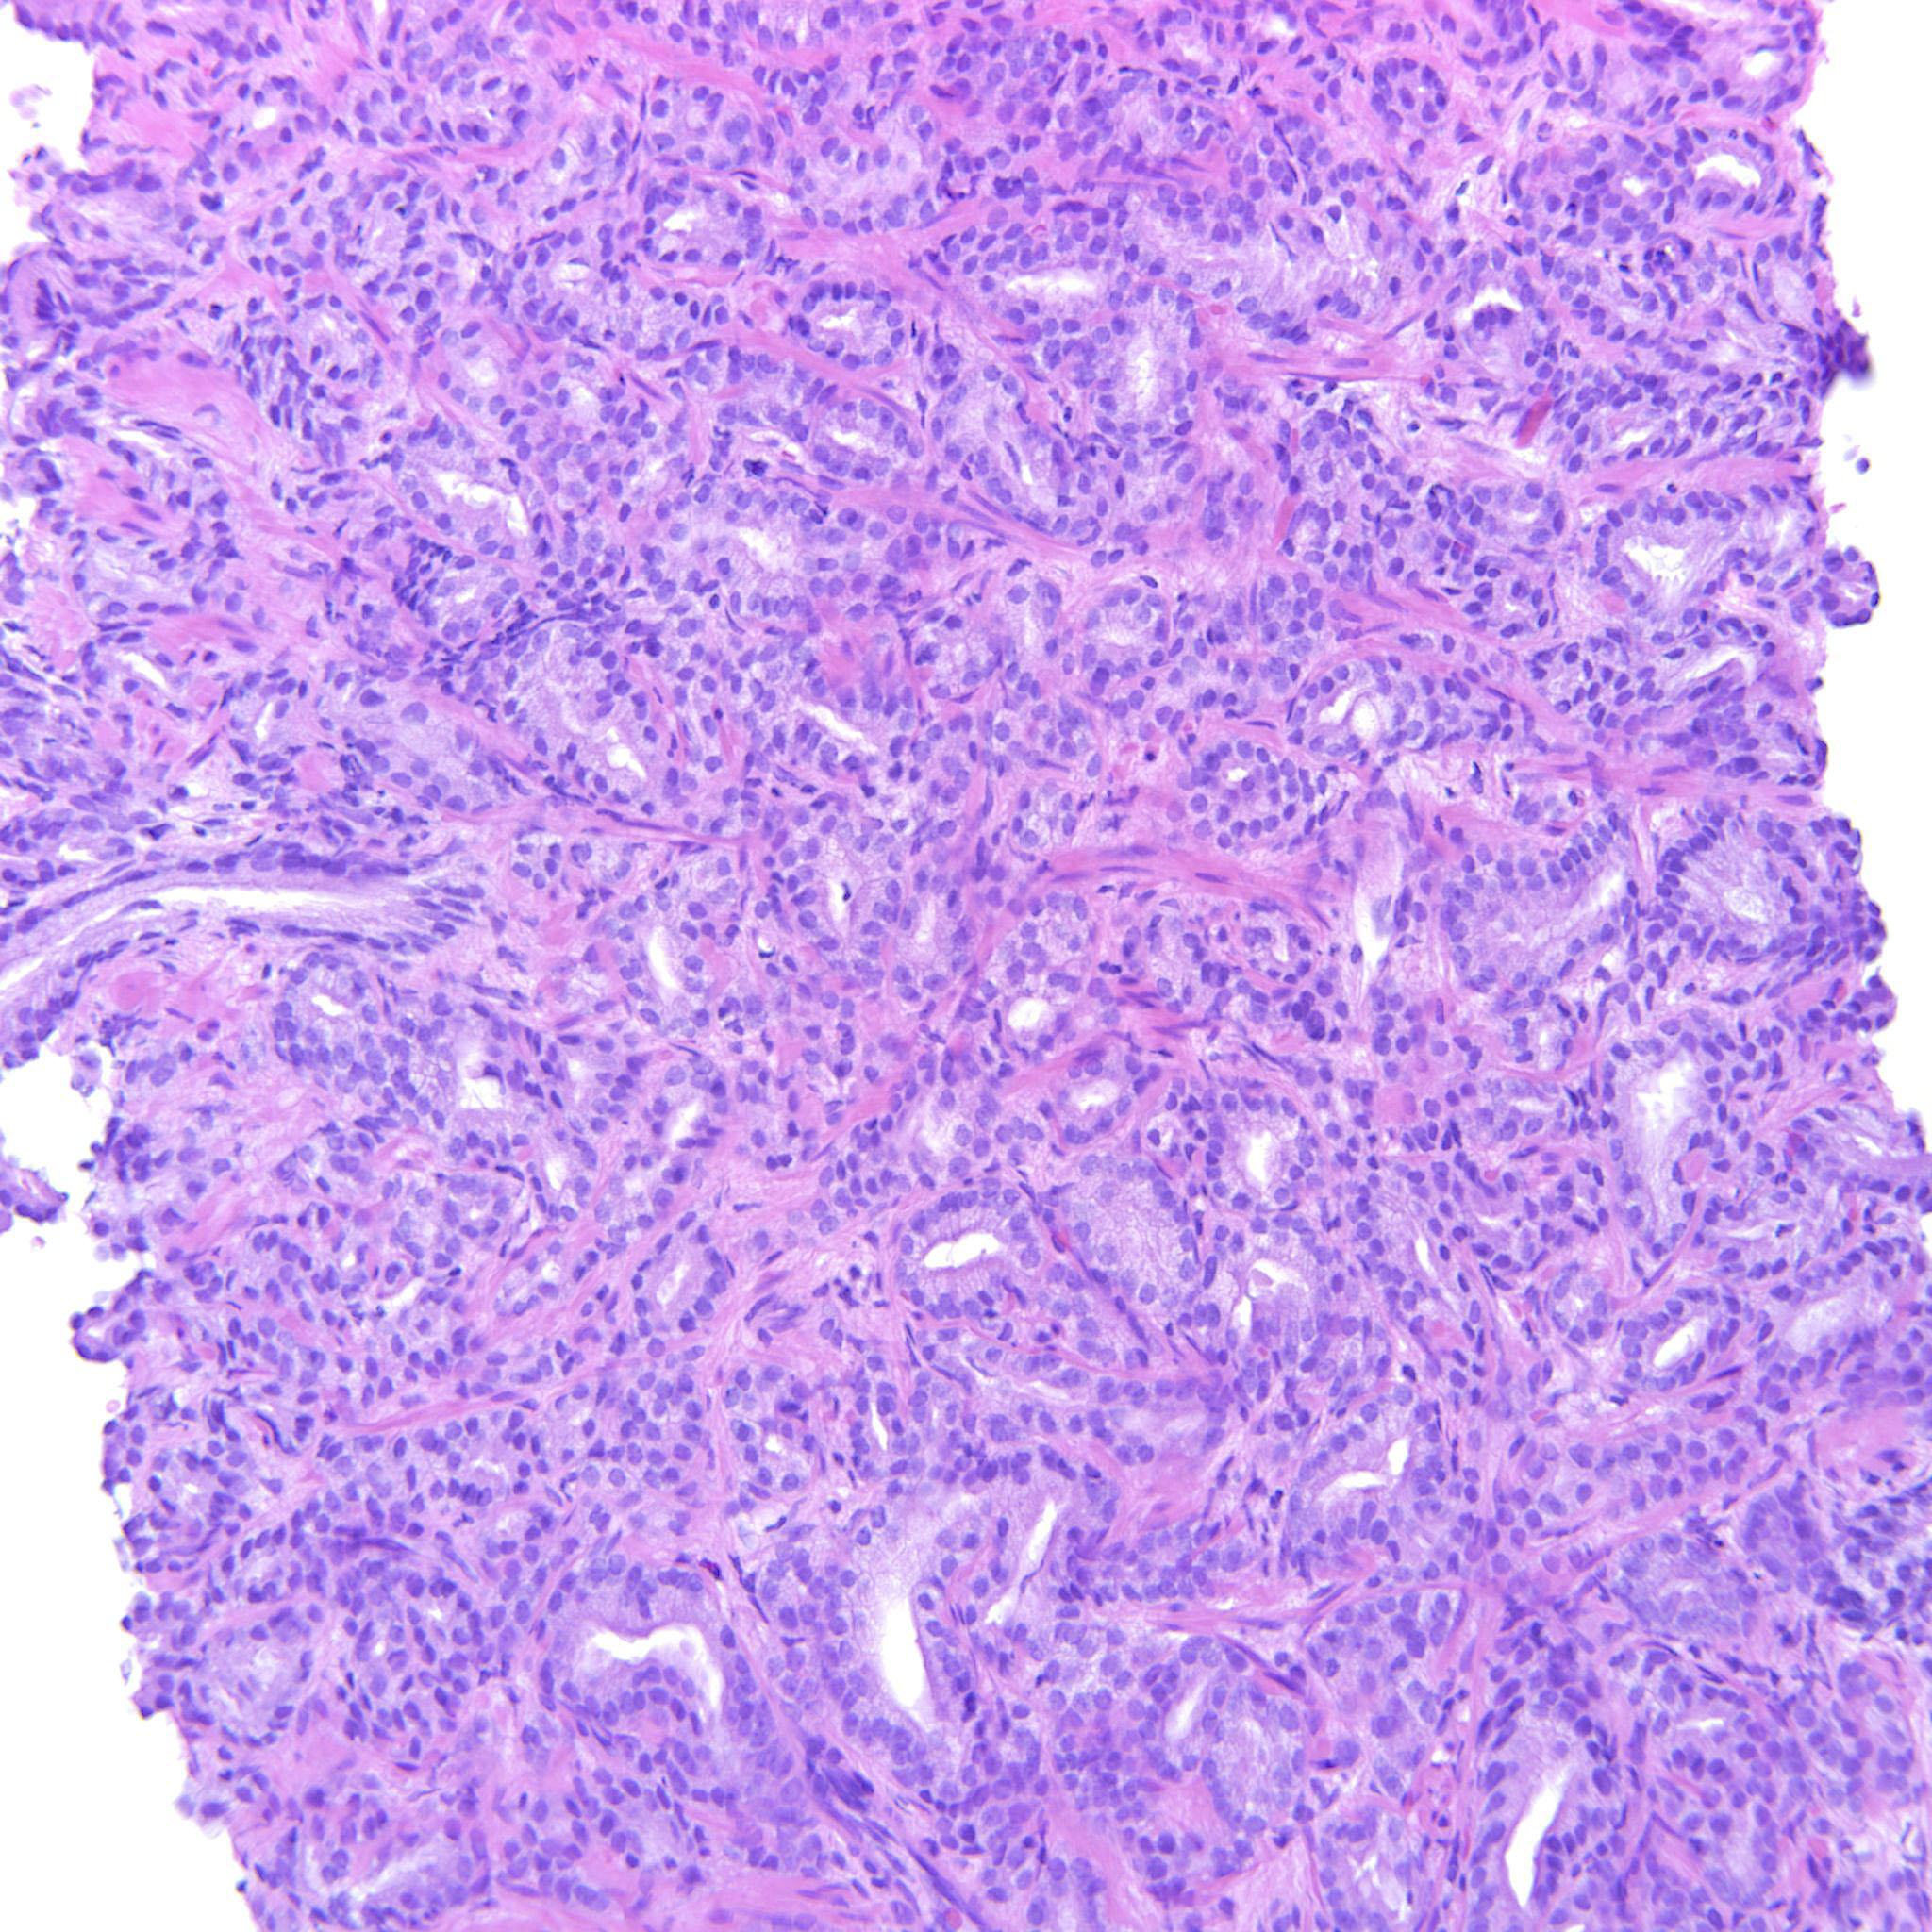

Consensus grade: GS 3+4=7 (ISUP 2)

one could also discuss a Score 6, but there is some glomerulation and congfluence

Mainly single glands. Some fused and poorly formed glands also

Case description (by case creator):

Some images only contain GP3 but there are also areas with poorly formed and fused glands justifying 347.